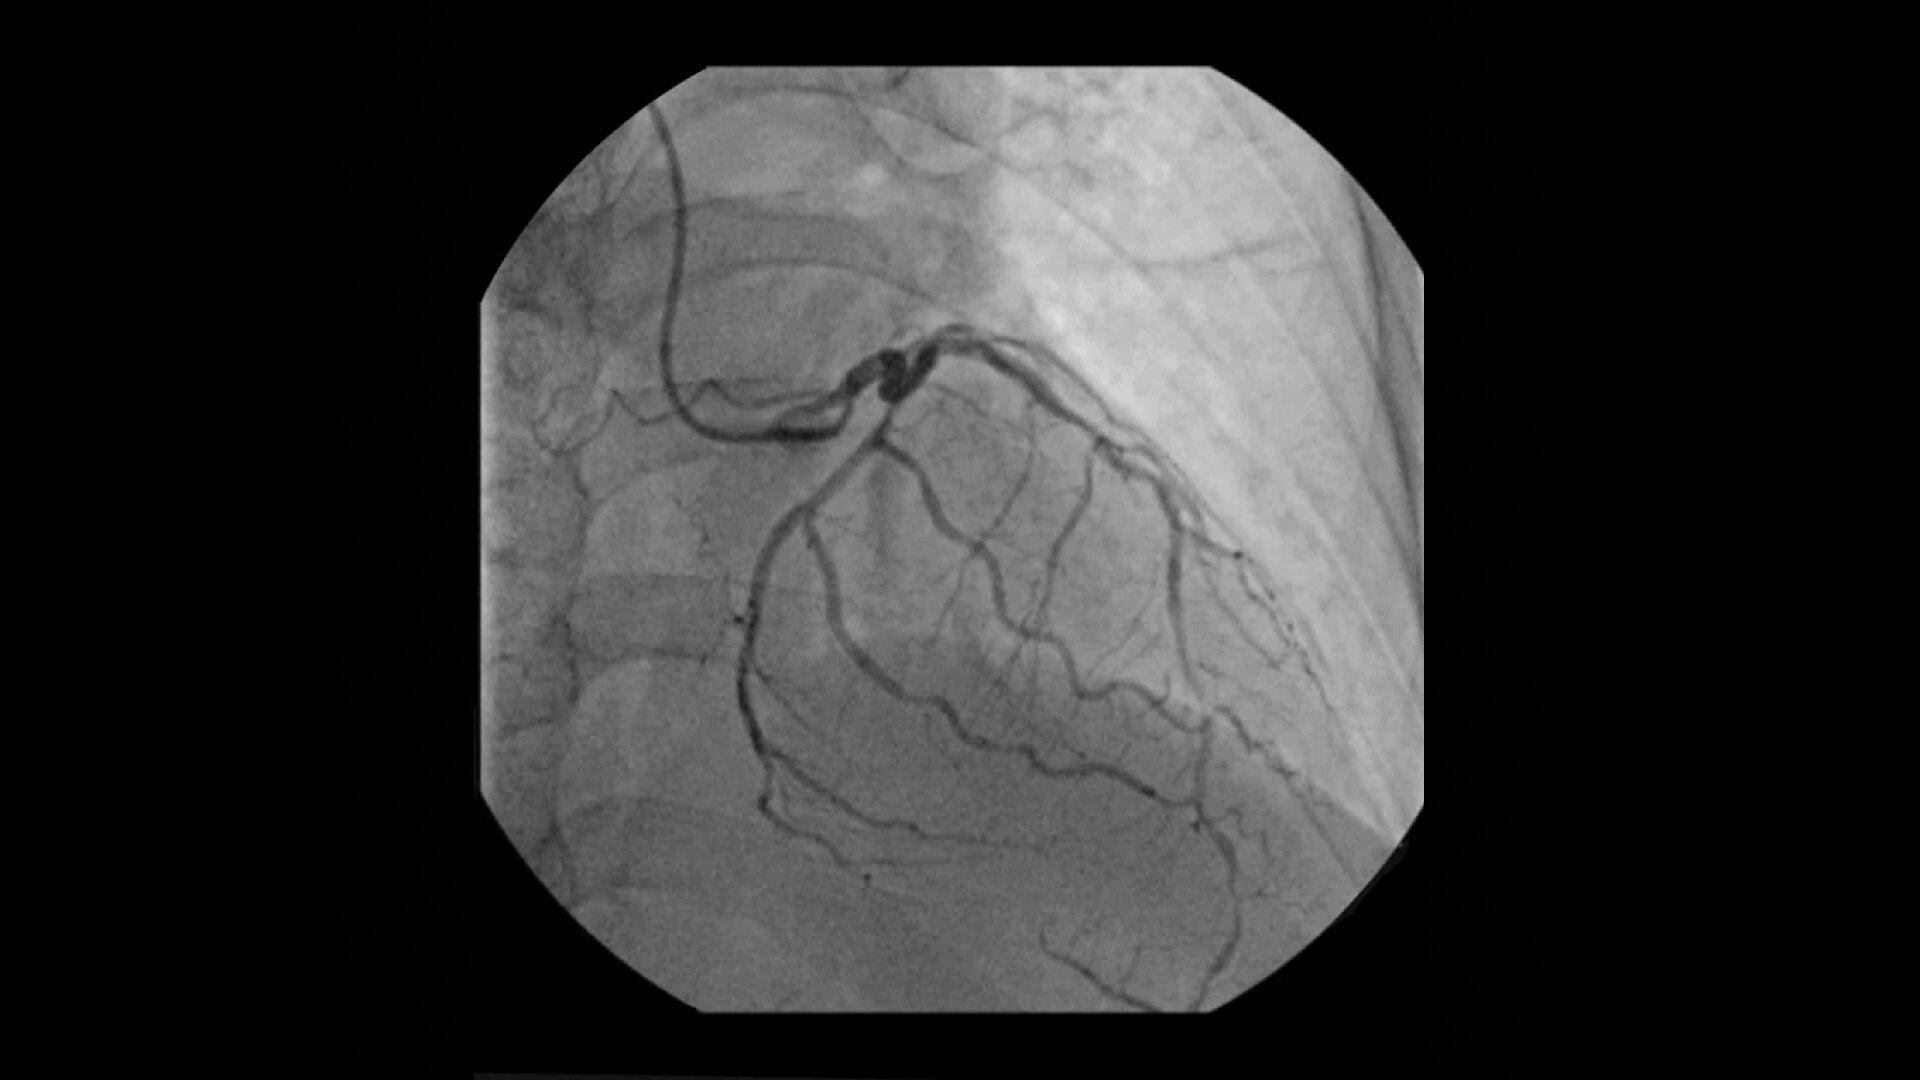

Achieve high-quality visualization necessary for complex cardiac procedures. OEC C-arms offer amazing image quality at low dose for efficient interventional imaging. Interventionalists and surgeons clearly see fine details of cardiac imaging, such as the border of the heart, leads, and small guidewires. Dynamic range management enables superb resolution, even with motion, during cardiac procedures.

See 0.014” guidewires in thoracic region or wire leads when placing biventricular pacemakers with the OEC Elite CFD flat detector, image processing, and 4K display.

Visualize moving interventional devices (catheters, stents) in vessels of the heart with the Cardiac Preset profile that automatically reduces blooming artifacts.